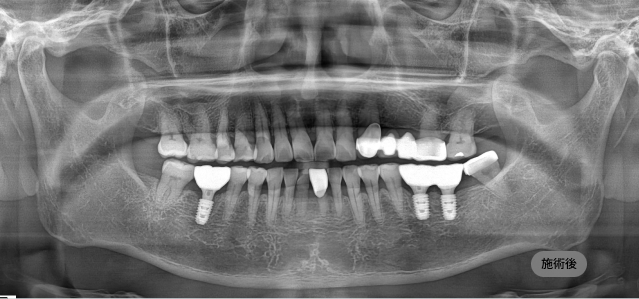

画面をドラッグして前/後を比較してみてください